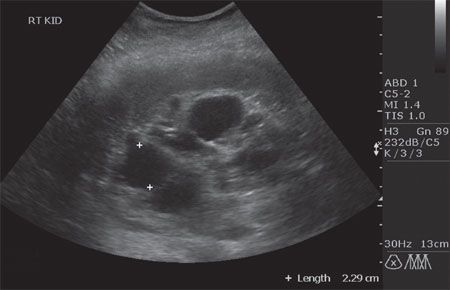

Applying the algorithm. Since you have evidence of CKD from serial MDRD estimates, you order an ultrasound and urinalysis according to the Algorithm. The ultrasound scan is shown in Figure 6. The urinalysis reveals 1+ urinary dipstick protein, and no sediment is appreciated. A spot Uprotein to Ucreatinine ratio is less than 0.3. Since ADPKD is not a glomerular disease, this result is not unexpected. By applying the results of serial GFR estimates, an ultrasound scan, urinalysis, and spot urinary protein determination, a diagnosis of CKD-3 caused by ADPKD can be entertained.

Figure 6 - Cysts are evident on this renal ultrasound scan of a patient with autosomal dominant polycystic kidney disease. The white crosses mark one cyst among others.